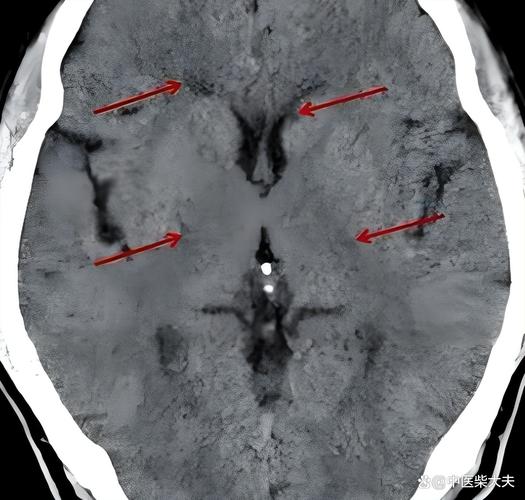

- 病灶小:这是它与普通脑梗最根本的区别,腔梗的直径通常小于1.5厘米,在CT上只是一个“小点”或“小洞”状的低密度影。

- 位置深:病灶位于大脑的“深加工车间”,如基底节、丘脑、脑干等,这些区域负责控制运动、感觉等精细功能。

- 无占位效应:因为病灶太小,不足以引起周围脑组织的水肿和移位,所以不会出现脑沟变浅、中线移位等情况,这是鉴别两者的一个重要依据。